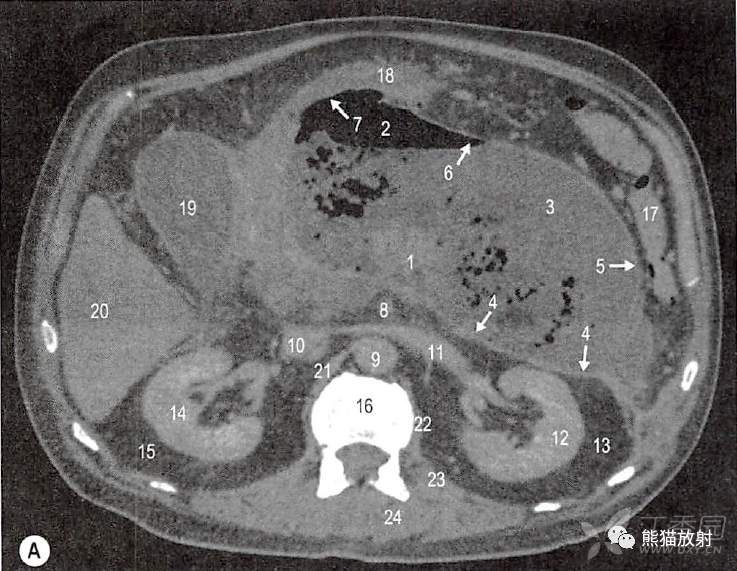

一例58岁慢性胰腺炎和胰周假性囊肿男性患者。

口服和静脉注射增强对比剂计算机扫描(CT轴位和矢状位)。

假性囊肿,包含气体和液体,胰周间隙扩大。融合筋膜的边界因为慢性炎症增厚,容易可见。

A.第2腰椎水平横断面;1.胰颈;2.前部气体的集聚(描述出胰周间隙);3.后部集聚的积液和碎片(描绘出胰周间隙);4.胰腺后融合筋膜(肾前筋膜融合十二指肠系膜右叶);5.胰周筋膜与左结肠系膜右叶融合;6.胰周筋膜深面到左结肠系膜前和收缩的小网膜囊;7.胃床上胰周前筋膜与小网膜囊腹膜融合;8.肠系膜上动脉;9.腹主动脉;10.下腔静脉;11.左肾静脉;12.左肾实质;13.左肾周间隙(不能与左肾后旁隙区分开);14.右肾实质;15.右肾周间隙(不能与右肾旁后间隙区别);16.第2腰椎体上部;17.脾曲;18.胃(被积液抬起或挤压);19.胆囊;20.肝右叶(5和6段);21.右膈脚;22.腰大肌起点;23.左侧腰方肌;24.左竖脊肌。